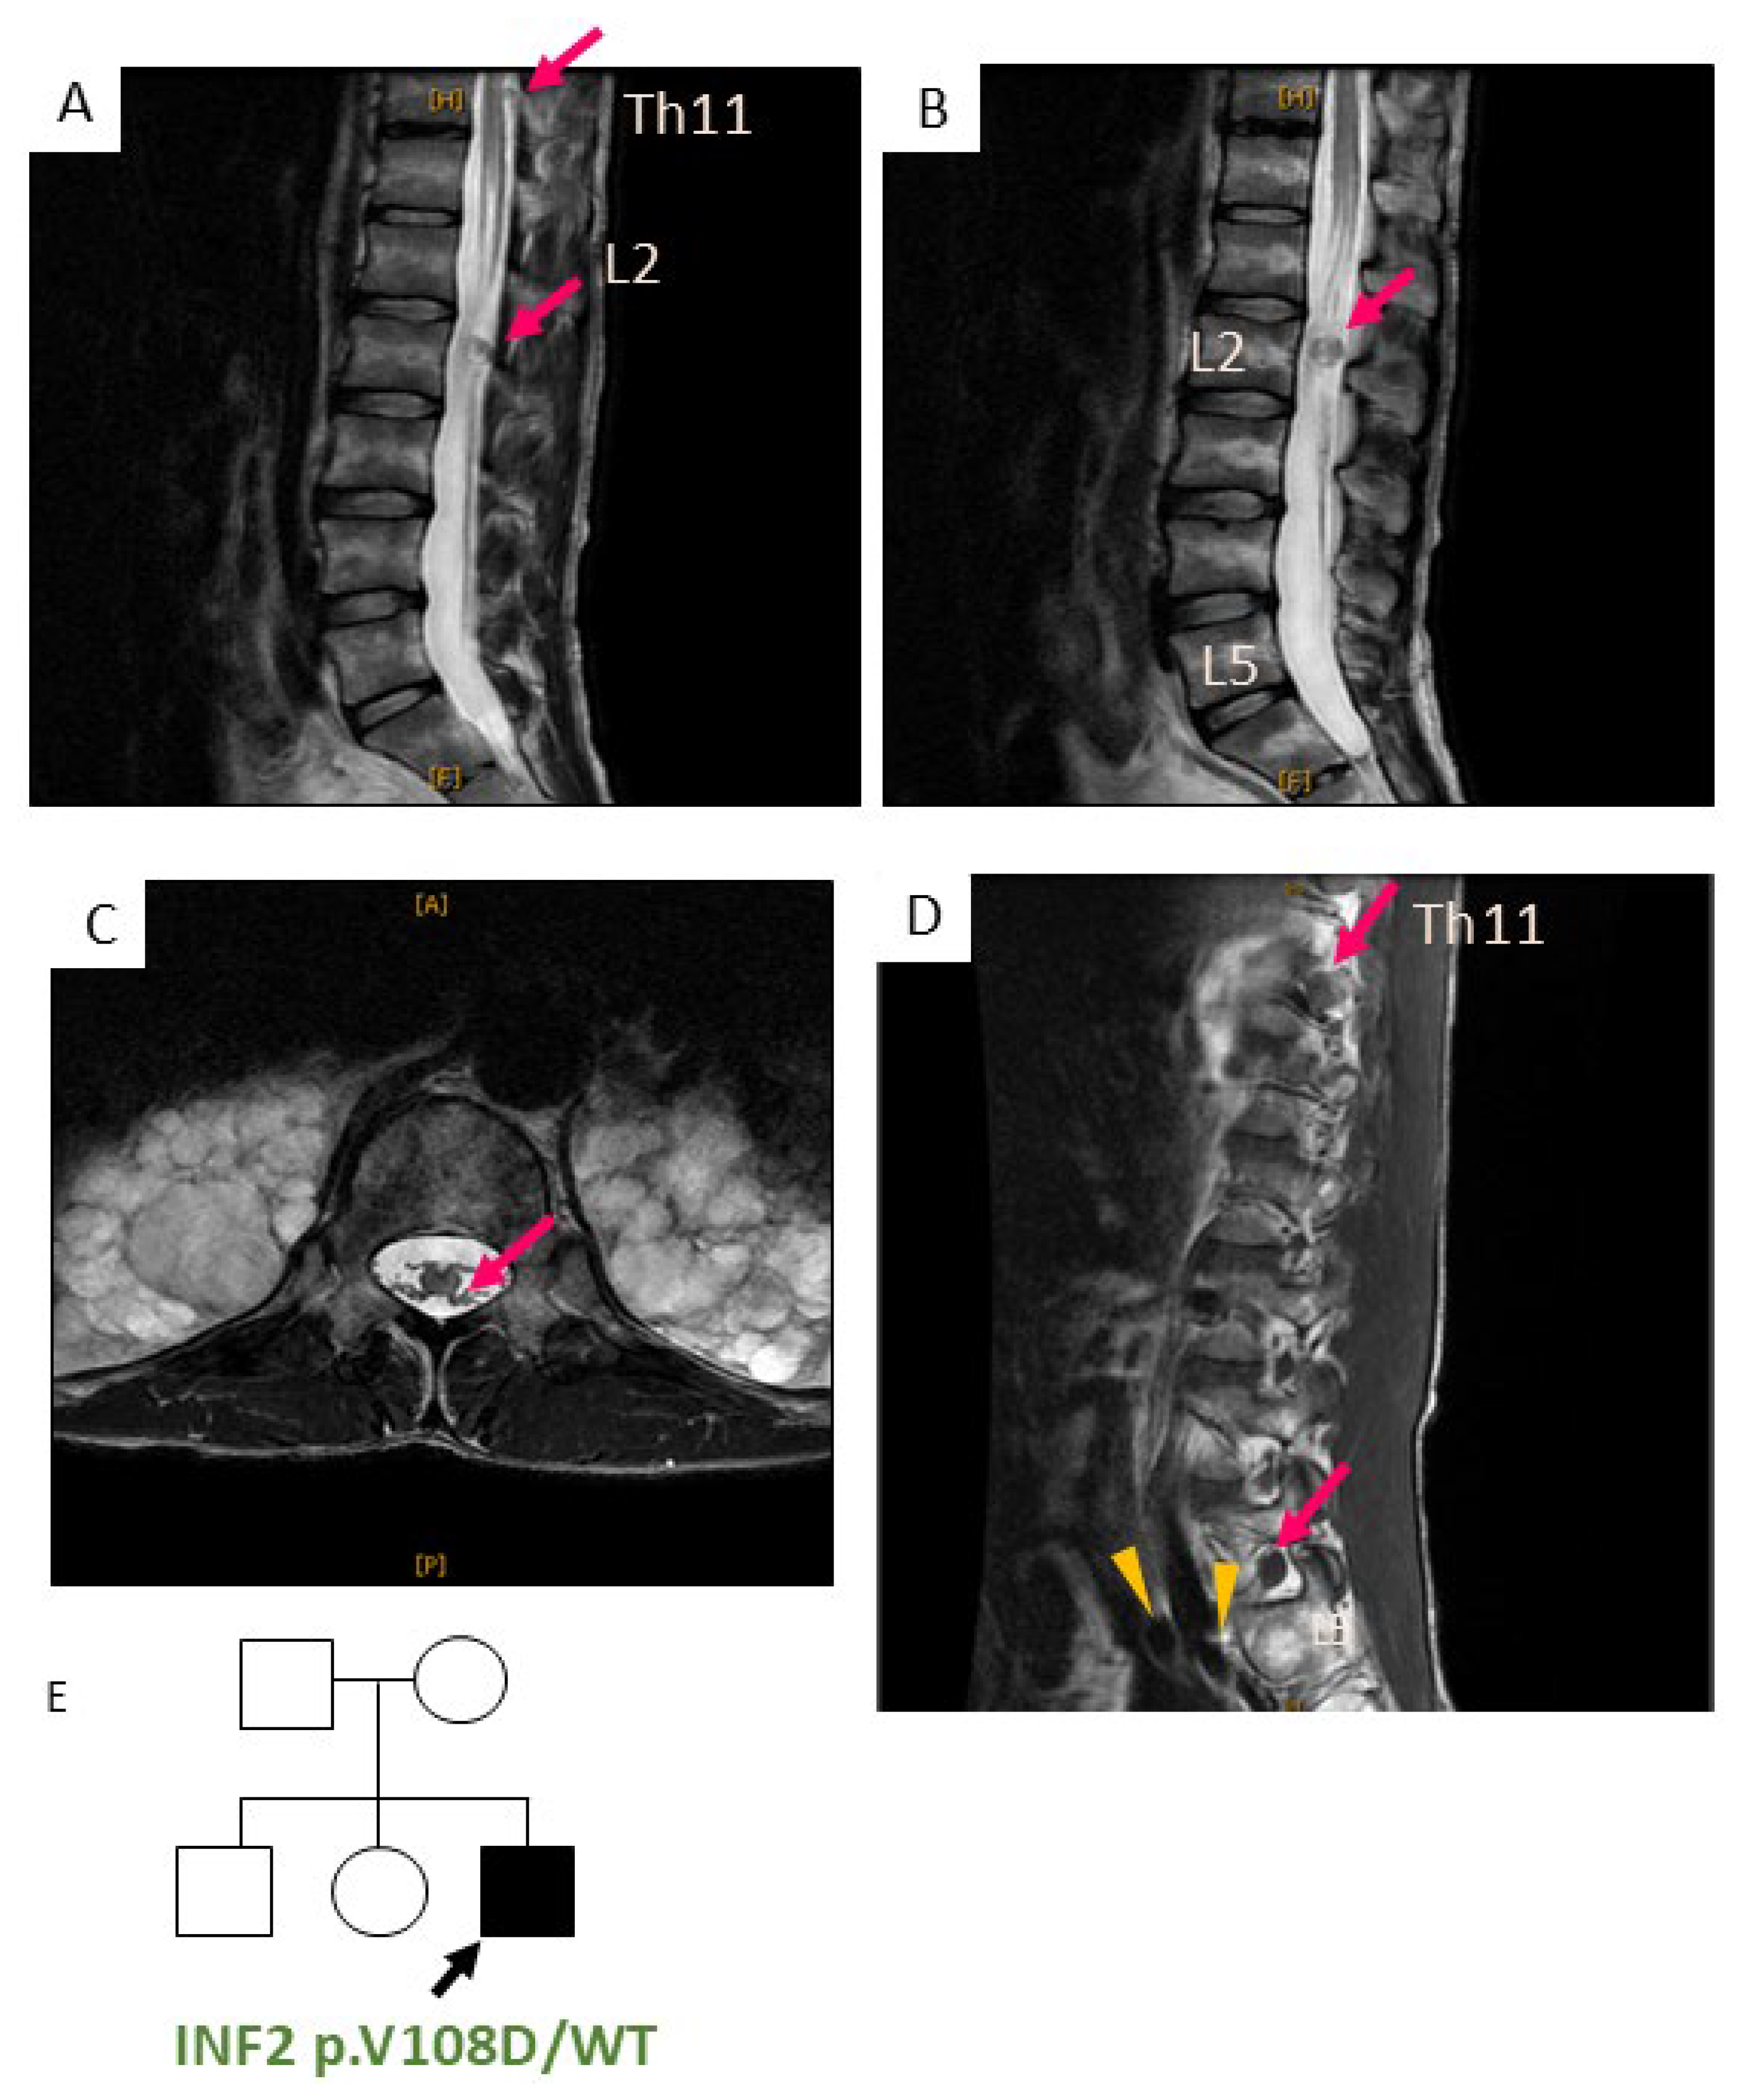

- Park, J.H.; Kwon, H.M.; Nam, D.E.; Kim, H.J.; Nam, S.H.; Kim, S.B.; Choi, B.O.; Chung, K.W. INF2 mutations in patients with a broad phenotypic spectrum of Charcot-Marie-Tooth disease and focal segmental glomerulosclerosis. J. Peripher. Nerv. Syst. 2023, 28, 108–118. [Google Scholar] [CrossRef]